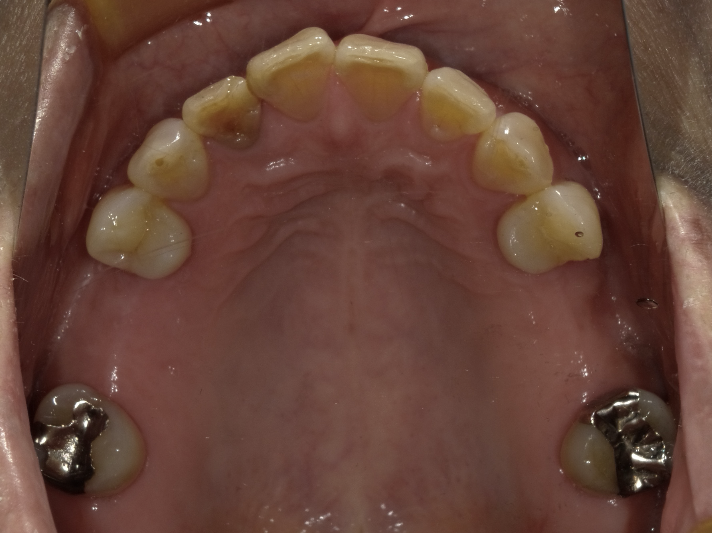

虫歯治療decay

インプラントimplant

歯周病perio

咬合治療occlusion